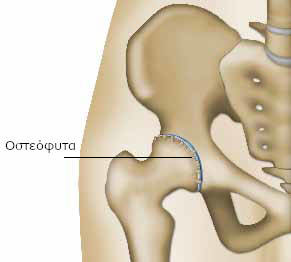

Εξαιτίας της φθοράς του χόνδρου, οι περιοχές των οστών έρχονται σε άμεση επαφή. Η επιφάνεια των οστών γίνεται άγρια και προκαλούνται τριβές κατά την κίνηση της άρθρωσης.

Η ολίσθηση της κεφαλής του μηριαίου στην κοτύλη γίνεται δύσκολη. Σταδιακά, το οστό παραμορφώνεται. Δημιουργούνται οστικές προεξοχές (τα οστεόφυτα), που περιορίζουν ακόμη περισσότερο την κινητικότητα της άρθρωσης.

Η ακτινογραφία είναι η τεχνική, που χρησιμοποιεί ακτίνες (τις ακτίνες X), για να δούμε τα οστά στο εσωτερικό του σώματος. Δεν επιτρέπει όμως να δούμε το χόνδρο. Η σημαντική ελάττωση του «διαστήματος» ανάμεσα στην κεφαλή του μηριαίου και την κοιλότητα της λεκάνης στην οποία θηλυκώνει (κοτύλη), δείχνει ότι το πάχος του χόνδρου μεταξύ των οστών μειώνεται.

Με τις ακτινογραφίες διαπιστώνουμε σταδιακές παραμορφώσεις του οστού και την εμφάνιση μικρών προεξοχών (οστεόφυτα). Ορισμένες φορές, χρειάζονται πιο εξειδικευμένες τεχνικές, όπως η αξονική και κυρίως η μαγνητική τομογραφία, που επιτρέπουν να αξιολογήσουμε καλύτερα την κατάσταση του χόνδρου και των μυών.